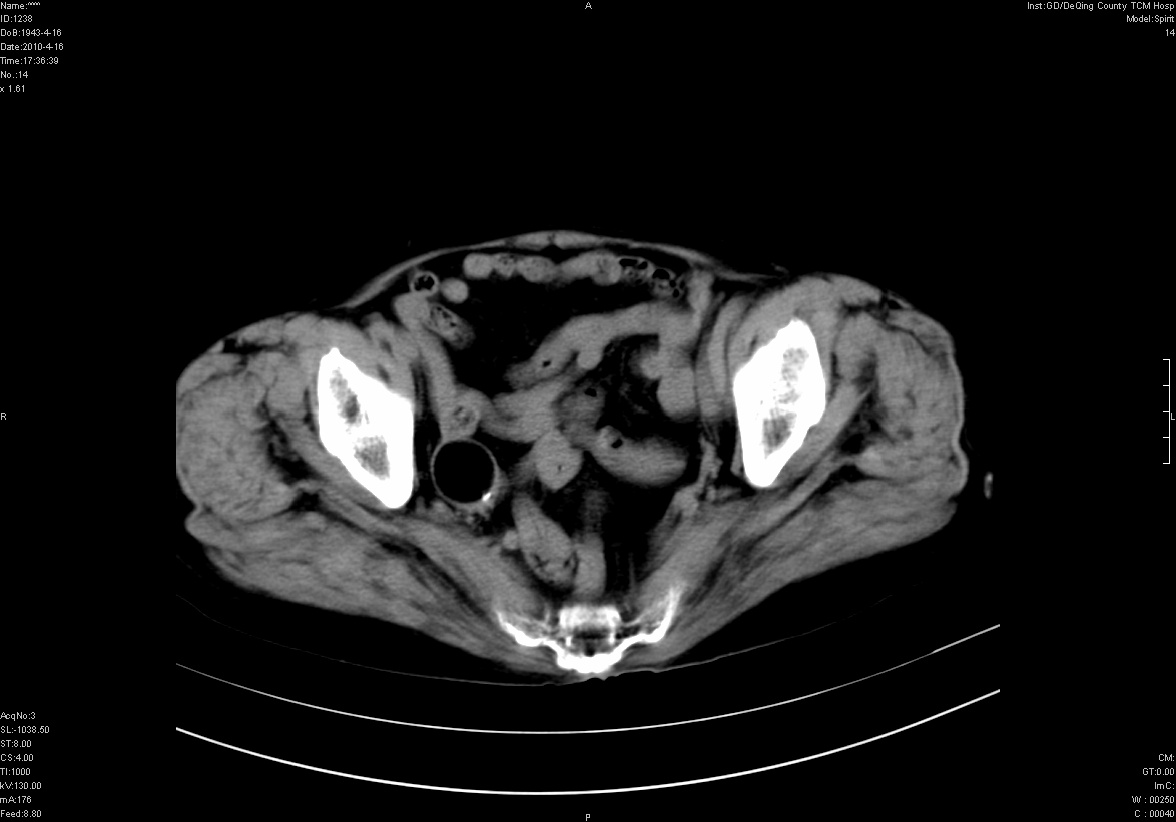

标题: CT25796:女,60岁,腹痛5天,请会诊??? [打印本页]

标题: CT25796:女,60岁,腹痛5天,请会诊???

是要我考虑粪石吗?引起阑尾炎

考虑卵巢畸胎瘤。

支持右侧盆腔畸胎瘤。

畸胎瘤

右侧附件畸胎瘤

不太像畸胎瘤,粪石。

考虑右侧卵巢畸胎瘤。

考虑右侧卵巢畸胎瘤

右侧卵巢畸胎瘤可能。